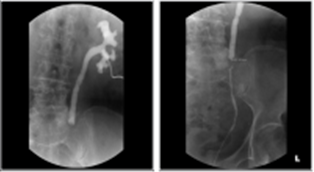

촬영방법

1) Male: 병원에 여러가지 시행방법이 있겠으나 교과서적으로는 10Fr Foley cath를 준비한 후에 ballon을 fossa navicularis에 넣고 1-2cc 정도의 saline을 넣어 balloning을 한다. 그리고 contrast (100%)를 6-10cc 정도 injection하며 supine AP, both oblique를 찍는다. 그 이상의 양으로 하게 되면 extravasation(into the corpus spongiosum and penile vein)의 가능성이 있게 된다. oblique는 35‘-45’를 유지시키며, dependent leg의 knee와 hip을 bent시킨다. 그리고 이런 urethrogram은 low dose radiation이 유리하다.

2) Female: double balloon Foley cath를 이용한다. balloon은 bladder neck에 유치시키며, 두번째 balloon은 labia majora에 유치시키고 촬영하며, 이후 촬영방법은 male과 같다.